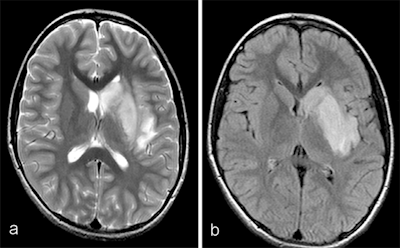

MRI demonstrated findings consistent with acute infarction without microhemorrhages (a, b, and c), along with focal irregular narrowing and banding of the proximal M1 segment of the left middle cerebral artery with a slightly reduced distal flow (d), according to Mirzaee and colleagues. Images courtesy of the RSNA.There are many reasons for stroke in children, ranging from "arterial dissection, embolic or thrombotic stroke, cerebral vasculitis in the context of systemic disease (including Kawasaki disease), and genetic disorders with arteriopathy," Mirzaee and colleagues wrote. Yet their best diagnosis was that the child's stroke had been caused by focal cerebral arteriopathy.